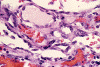

Panel A, B and F are taken from the dermal-epidermal junction. Panel B, C, D, and E are taken from the same area. Panel F, G, H, and I are taken from the same area

The tumor appears to be centered on the dermis and does not involve breast parenchyma in the sections examined A (not shown). On low-magnification (Panel A, B and F), the lesional tissue is a highly cellular and vascular tumor in the dermis. The large areas of hemorrhage ("blood-lake") and dilated vascular channels (Panel A, and F) probably correspond to the "red nodules and yellow patches" on physical examination. Although the tumor extends deeply into the subcutaneous tissue (not shown here), there is no evidence of invasion in to the epidermal layer (Panel A, B and F). The histology of this tumor varies in different areas. In some areas, it appears as a densely packed spindle cell tumor with exuberant and irregular and anastomosing vascular channels (Panel B, C, and D). The endothelial cells protrudes into the vascular channels and had enlarged, hyperchromatic nuclei with  prominent nucleli. In another area, the lesion contains numerous ectactic and anastomosing vascular channels (Panel F, G, H, and I). Pleomorphic changes are also prominent in the vascular cells in these areas. On immunohistochemistry, the tumor cells are immunoreactive for CD31, CD34 (not shown).